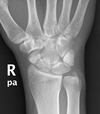

Colles’ fracture

Colles fracture ## Footnote Typically FOOSH forwards Extra-articular radial # with dorsal (posterior / back of hand) angulation and displacement